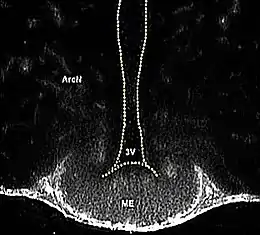

![]() ME= Eminencia media. 3V= tercer ventrículo. | ||

La eminencia media (ME en inglés) es una franja estrecha de tejido, comprendida entre el suelo del tercer ventrículo por arriba y la pars tuberalis de la adenohipófisis por abajo.

La eminencia media forma la pared inferior y el piso del tercer ventrículo.[2]

En un corte de plano frontal (transversal) del cerebro, la EM se ve como una franja estrecha de tejido nervioso, comprendida entre el suelo del tercer ventrículo por arriba y la pars tuberalis de la cual arranca el infundíbulo y la adenohipófisis por abajo.[6][3]